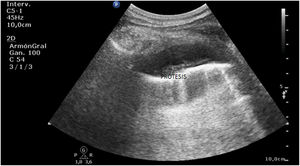

A las pocas horas, en el control sonográfico, se puede apreciar la endoprótesis (fig. 1) con sus pinzas (flechas en la figura 2) en la región del cuerpo gástrico, en la ventana esplenorrenal. A través de una endoscopia se recoloca la prótesis hasta su correcta ubicación. En seguimiento por ecografía, se comprueba la desaparición del dispositivo en el cuerpo del estómago (fig. 3).